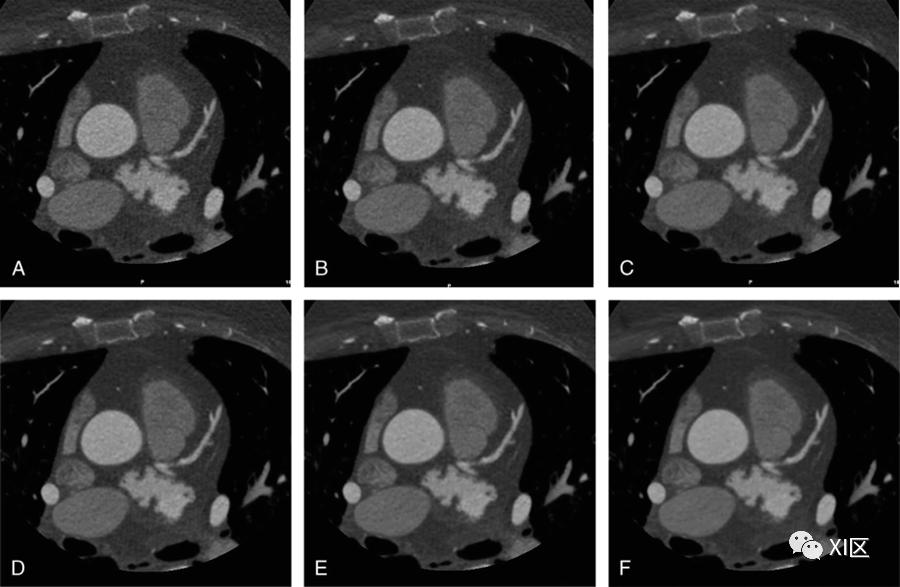

图2 用不同水平的ASiR-V算法重建的CT图像的比较。一位57岁女性,患有结直肠癌,伴有单肝转移,腹部静脉期轴位CT扫描(黑色箭头)。扫描是在100 kVp下通过管电流调制获得的(mAs范围,99–170);用(A)滤波反投影(FBP)和ASiR-V在20%(B)、40%(C)、60%(D)、80%(E)和100%(F)强度重建原始数据。随着ASiR-V强度水平的增加,图像噪声逐渐减少,而低衰减转移仍然可见。此外,IR在对比度可检测性和噪声降低方面的改进导致了腹部动脉和静脉分支的更好描绘,甚至是远端小血管的更好描绘。